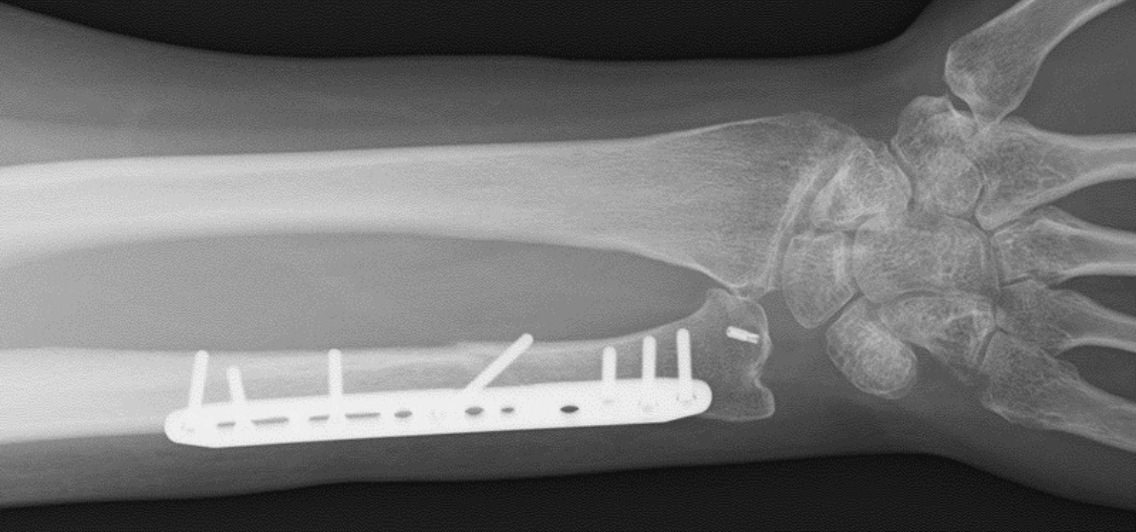

外傷(骨折、脱臼)

• 上肢(特に手や肘)の新鮮骨折や脱臼(小児例も含む)

• 骨折後の偽関節(骨折が治癒していない)

• 骨折後の変形治癒(変形している)

• 関節拘縮(関節が固くなっている)